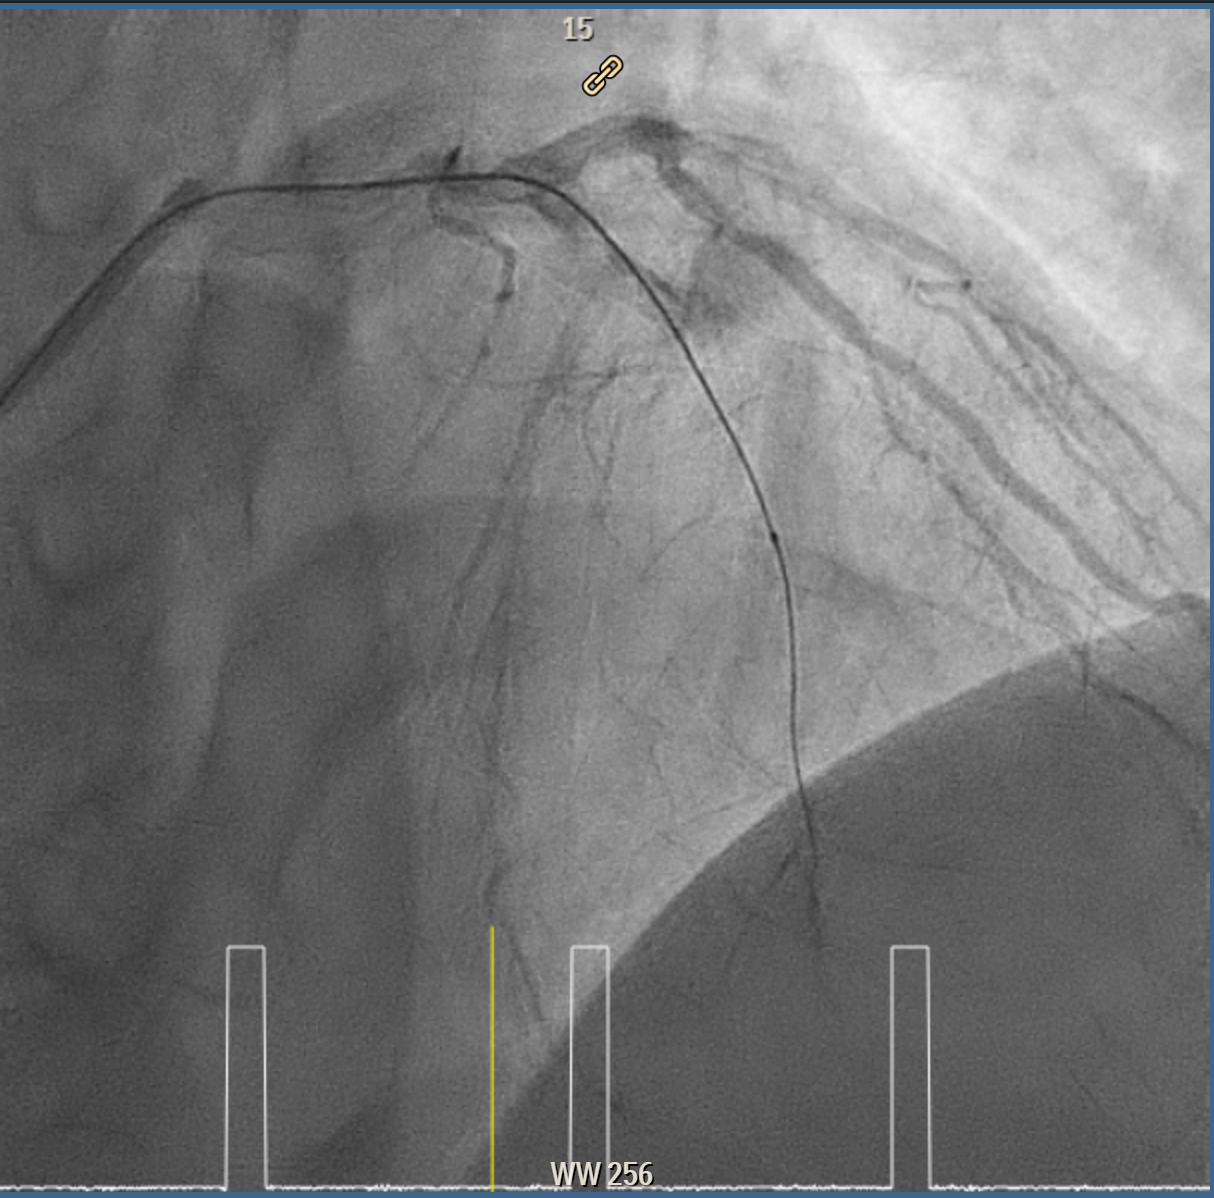

Coronary intervention was performed on a proximal LAD (pLAD) total occlusion via single right radial approach using 6F XB 3.5 guiding catheter. Initial antegrade attempts with RunThrough Floppy and Fielder-XT wires were unsuccessful due to buckling against the proximal cap. Wire strategy was escalated to Gaia Second wire with Finecross microcatheter support, allowing careful penetration of proximal cap and subsequent advancement through distal cap. True lumen position was confirmed with contrast injection through the microcatheter, and wire was then exchanged to a Fielder-XT wire to safely navigate to distal LAD (dLAD) and reduce risk of perforation. Lesion preparation was performed with stepwise predilatation, beginning with Sapphire 0.85 ¡¿ 5 mm balloon at 10–12 atm in pLAD to dLAD. Further predilatation was performed with Sapphire 2.0 ¡¿ 15 mm balloon at 12 atm from dLAD to mid LAD (mLAD) and higher pressure up to 16atm at pLAD. Despite multiple inflations, pLAD remained tight, prompting escalation with a Sapphire 2.5 ¡¿ 15 mm balloon at up to 18 atm and Scoreflex NC 3.0 ¡¿ 15 mm balloon at 8–12 atm to adequately prepare mildly calcified pLAD segment. Final predilatation achieved optimal luminal caliber. DCB was then performed, with m-dLAD treated using Magic Touch 2.25 ¡¿ 35 mm and the p-mLAD treated with Magic Touch 3.0 ¡¿ 40 mm. Both were deployed at 8 atm for 60 seconds. The procedure resulted in excellent luminal gain with no residual stenosis, recoil, or perforation.